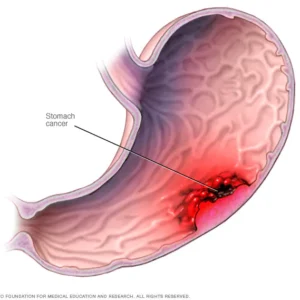

- سرطان ها

- سرطانی که از قسمت دیگری از بدن شروع می شود و به کبد سرایت می کند

- سرطان کبد